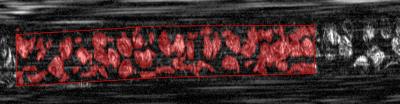

Using the new microscope, the researchers imaged the blood flowing through a vessel in the lower lip of a volunteer. They successfully measured the average diameter of the red and white blood cells and also calculated the percent volume of the different cell types, a key measurement for many medical diagnoses.

The device relies on a technique called spectrally encoded confocal microscopy (SECM), which creates images by splitting a light beam into its constituent colors. The colors are spread out in a line from red to violet. To scan blood cells in motion, a probe is pressed against the skin of a patient and the rainbow-like line of light is directed across a blood vessel near the surface of the skin. As blood cells cross the line they scatter light, which is collected and analyzed. The color of the scattered light carries spatial information, and computer programs interpret the signal over time to create 2-D images of the blood cells.

"An important feature of the technique is its reliance on reflected light from the flowing cells to form their images, thus avoiding the use of fluorescent dyes that could be toxic," Golan says. "Since the blood cells are in constant motion, their appearance is distinctively different from the static tissue surrounding them." The team's technique also takes advantage of the one-way flow of cells to create a compact probe that can quickly image large numbers of cells while remaining stationary against the skin.